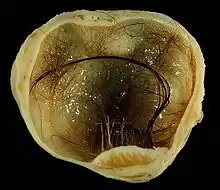

| A small (4 cm) dermoid cyst of an ovary, discovered during a C-section | |

A dermoid cyst is a teratoma of a cystic nature that contains an array of developmentally mature, solid tissues. It frequently consists of skin, hair follicles, and sweat glands, while other commonly found components include clumps of long hair, pockets of sebum, blood, fat, bone, nail, teeth, eyes, cartilage, and thyroid tissue.

Large ovarian cyst